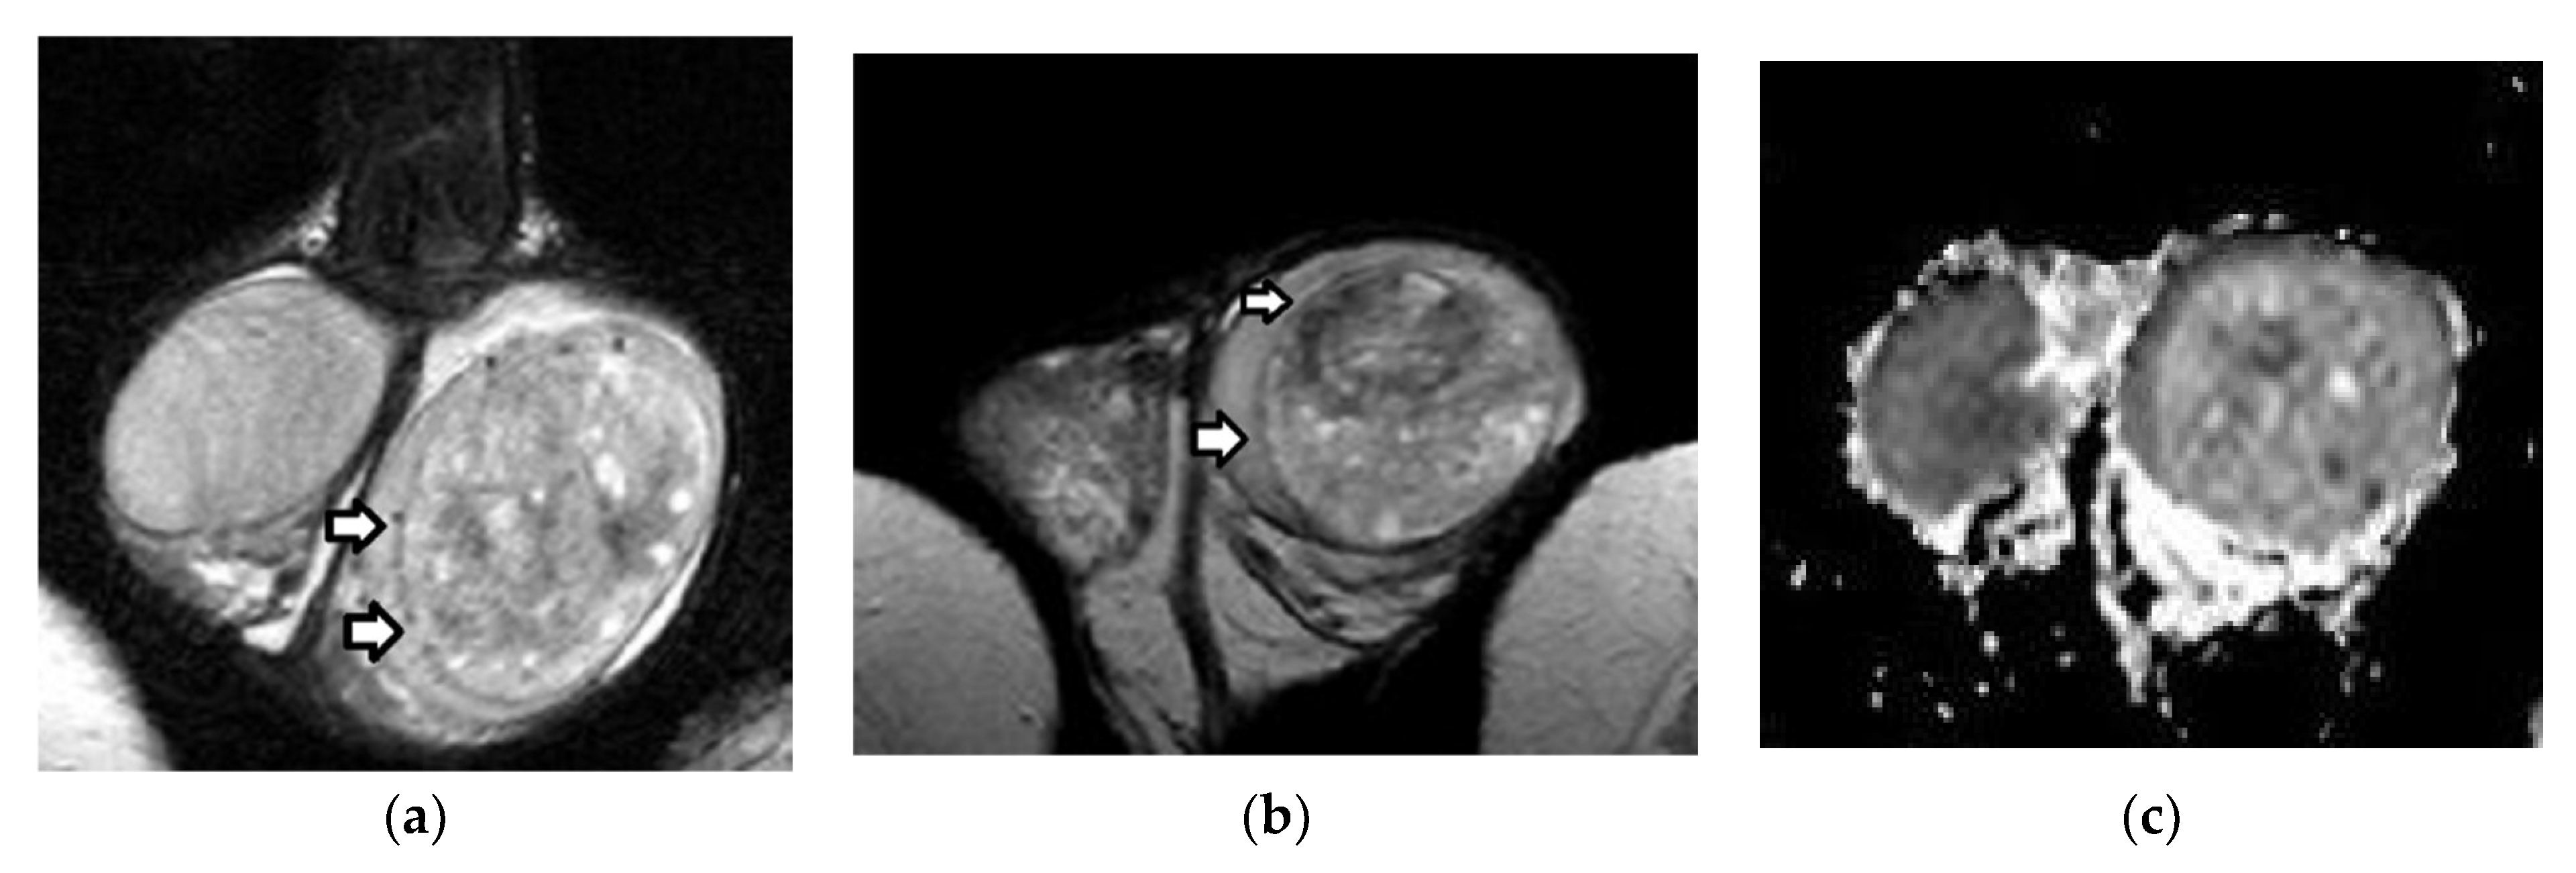

3.1. MRI Findings of TGCTs

5. Histological Characterization of TGCTs

6. Local Staging of TGCTs